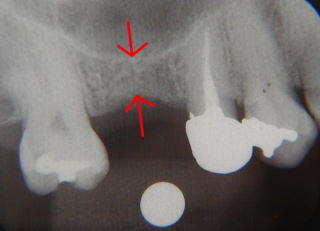

抜歯してから4ヶ月後。 利用できる骨の量は、矢印間で4ミリ。従来方法では入れるのは不可能なケースです。 |